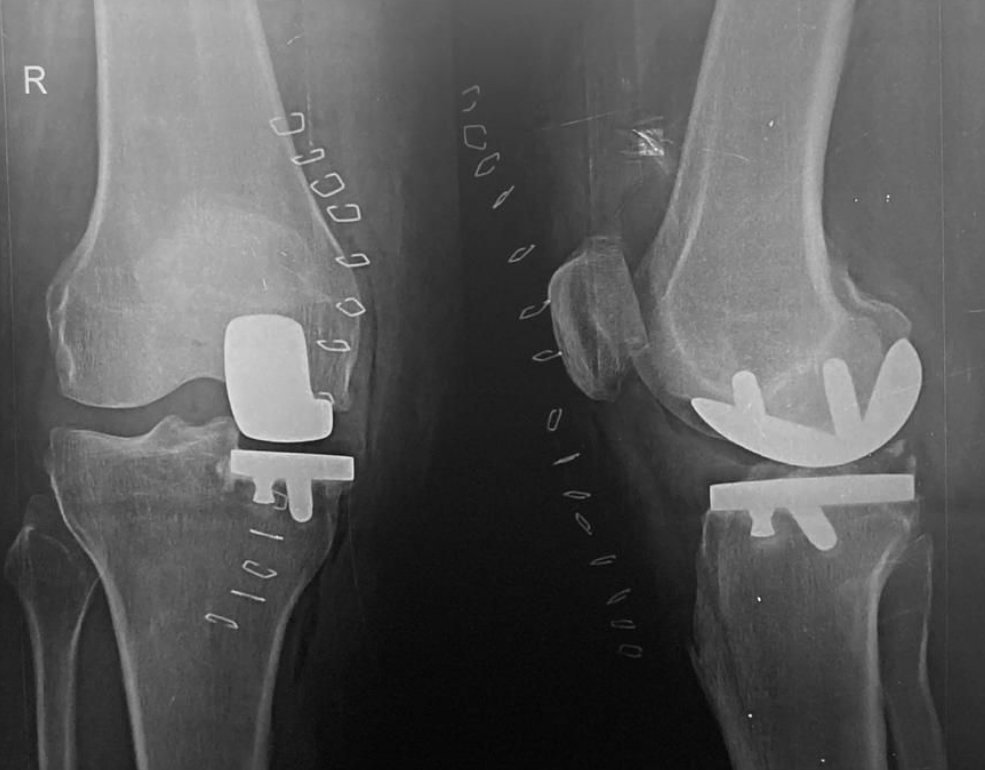

After Surgery

After